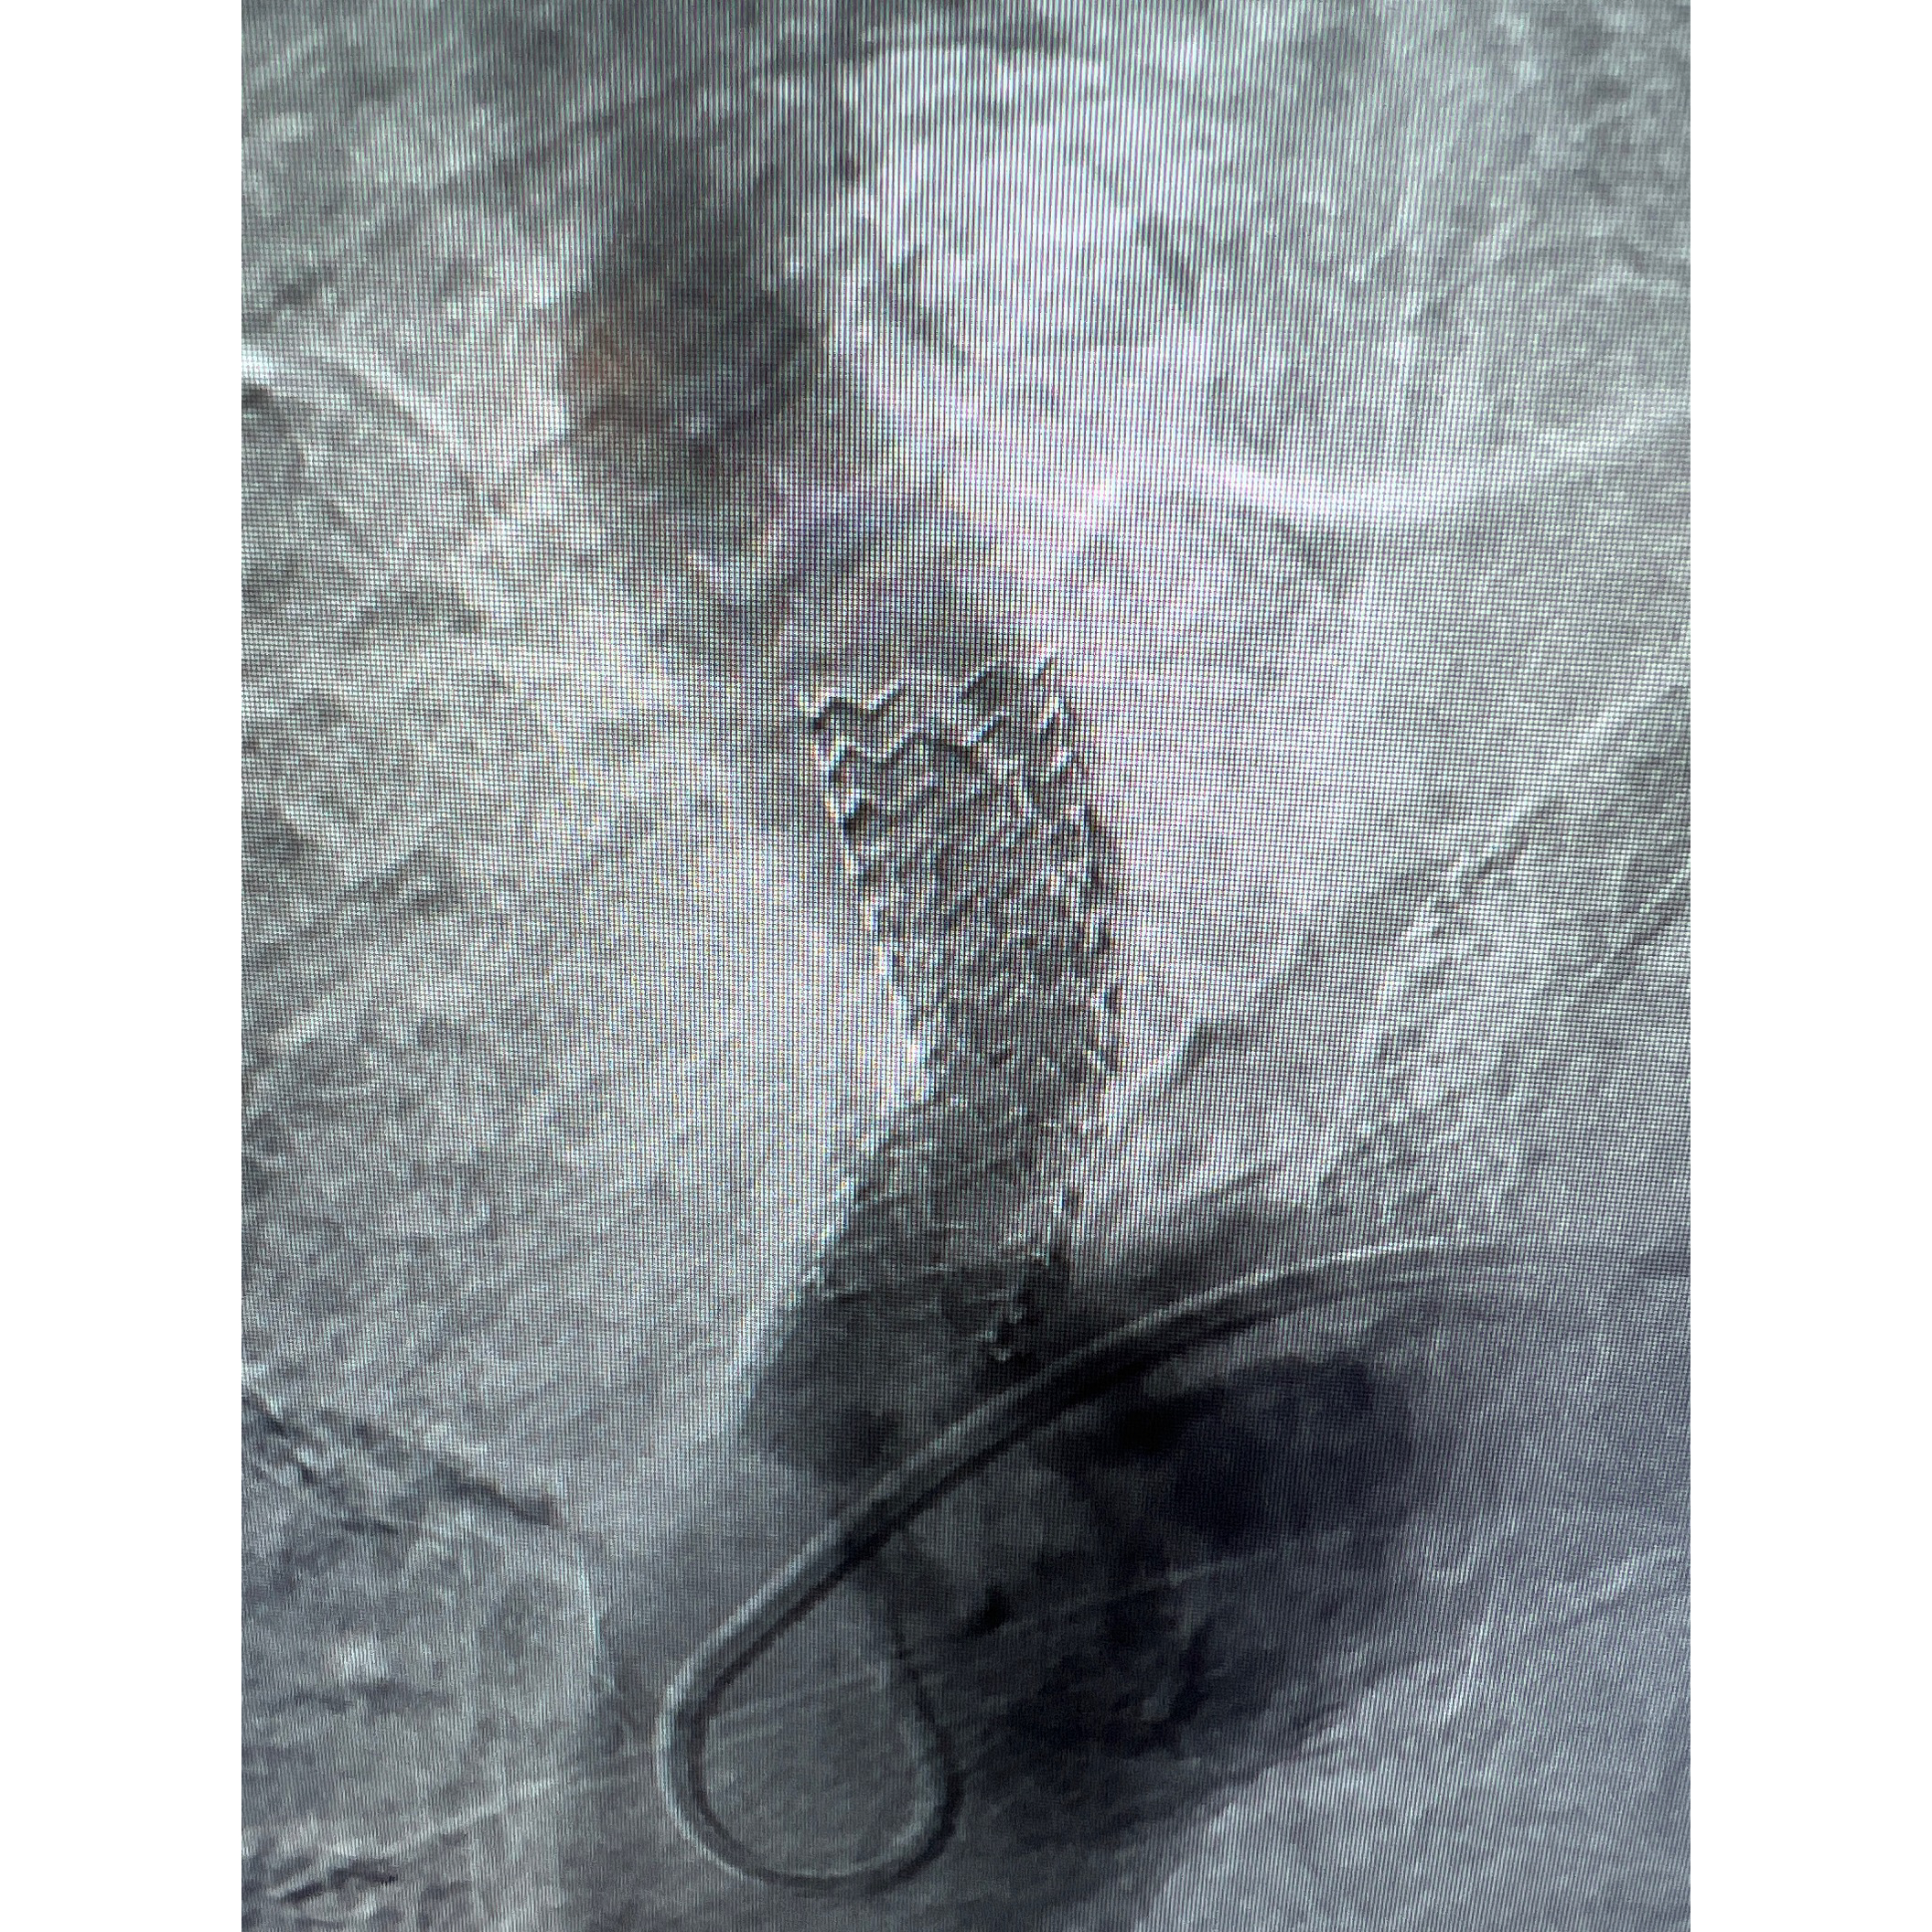

A 70-year-old female with a history of peripheral vascular disease presented with claudication in both arms, manifested as pain in both arms. Her left subclavian was stented months prior to presentation. An aortogram revealed severe stenosis of the innominate artery (Figure 1). Since multiple attempts to cross the lesion antegrade from the femoral access site were unsuccessful, we proceeded with the successful deployment of an embolic protection filter in the right internal carotid artery via our right radial artery access site (Figure 2). Using the right radial artery, we passed a long run-through guidewire into the distal abdominal aorta. Due to severe aortic tortuosity, we were unable to snare the wire from the aorta. Therefore, we upsized the radial sheath to 7 French over both wires (runthrough and bare). Using a support catheter, we exchanged the runthrough wire for a Glidewire Advantage. We advanced an 8 x 29mm balloon expandable stent to the area of innominate stenosis and deployed it (Figure 3). We postdilated the stent with a 14mm balloon. Angiography demonstrated adequate expansion. On follow up, the patient was without claudication and had triphasic flow in the innominate and left subclavian arteries.